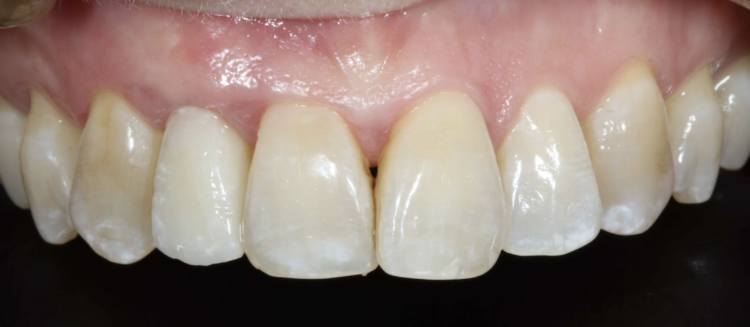

Three-year review

A three-year review of the final outcome displayed adequate hard and soft tissue volume with complete papilla infill and a pleasing outcome for the patient.